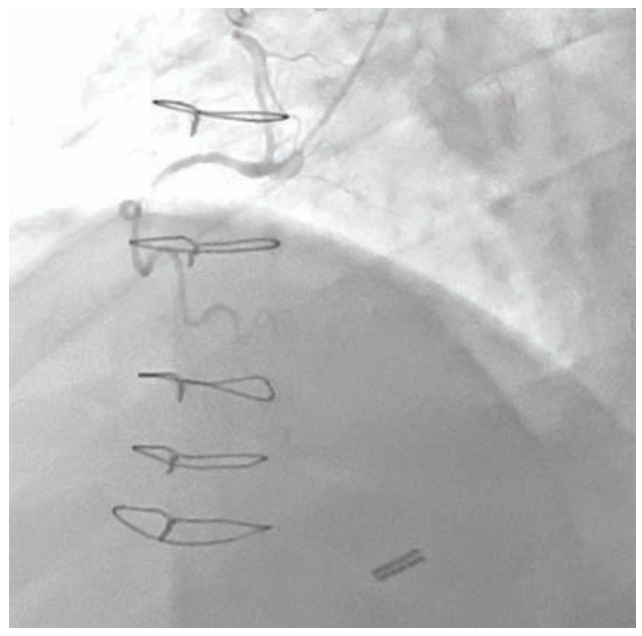

Dual access was achieved with a 7 French Amplatz Left (AL)-1 guide catheter and a 7 French Extra Backup (EBU) 3.75 guide catheter. Based on dual-injection angiography, the proximal cap was ambiguous due to a tortuous right ventricular (RV) marginal branch and the occlusion was long (>20 mm) (Figure 1). Therefore, we decided to attempt retrograde techniques first. After administering heparin to a goal activated clotting time (ACT) of >350, a workhorse wire was advanced through a low-profile microcatheter into the first septal perforator. The wire was exchanged for a specialty wire that was used to cross septal collaterals. We had difficulty advancing the microcatheter into the septal perforator, as it was jailed with a previously placed stent (Figure 2). Here, we used a 1.5 mm x 20 mm TAKERU balloon to dilate the stent struts. We were able to advance the microcatheter into the septal perforator and into the distal vessel (Figure 3). The connection was made with a reverse controlled antegrade and retrograde tracking (R-CART) technique (Figure 4). Overlapping drug-eluting stents were placed and aggressively post dilated. Final angiography demonstrated no residual stenosis, dissection, or perforation (Figure 5). The patient was placed on dual antiplatelet therapy for six months.